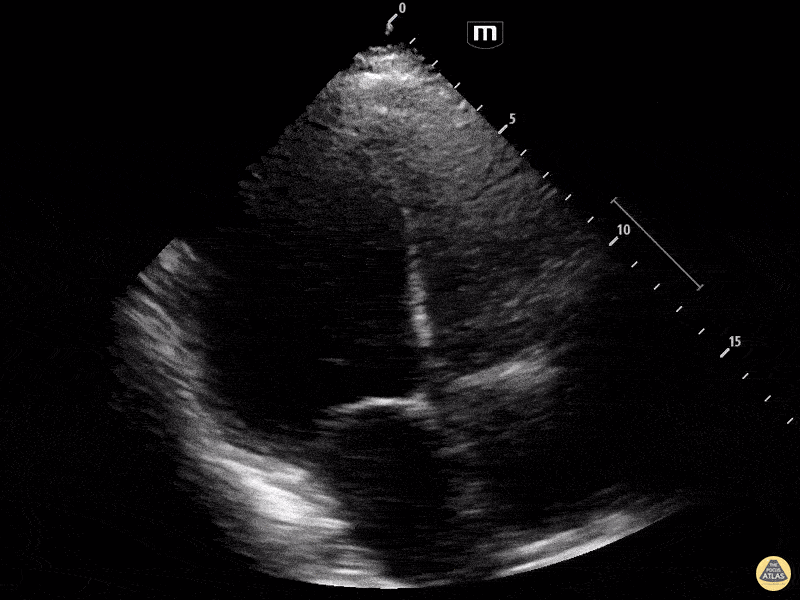

Other Cardiac Pathology - Viral vs. Postpartum Cardiomyopathy A4C

These images are from a bedside echo performed on a 29-year-old female who presented in significant respiratory distress to the ER. She had no significant medical history besides giving birth a few months prior. Required significant respiratory support and was found to have significantly reduced cardiac function on echo secondary to viral vs. postpartum cardiomyopathy. Dakota Nerland, DO PGY-3; Marion Memmot, DO PGY-1